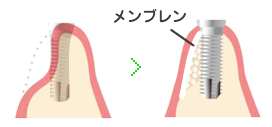

GBR

GBRとはGuided Bone Regenerationの頭文字からなる略語で、「骨誘導再生法」とも呼ばれています。インプラントが歯槽骨内に収まらない場合に行います。

GBRとはGuided Bone Regenerationの頭文字からなる略語で、「骨誘導再生法」とも呼ばれています。インプラントが歯槽骨内に収まらない場合に行います。

インプラント埋入と同時に骨の足らない部分に人工膜を使用して骨の再生を促し造成を行う方法と、最初に骨を移植・固定し再生させた後からインプラントを埋入する方法があります。